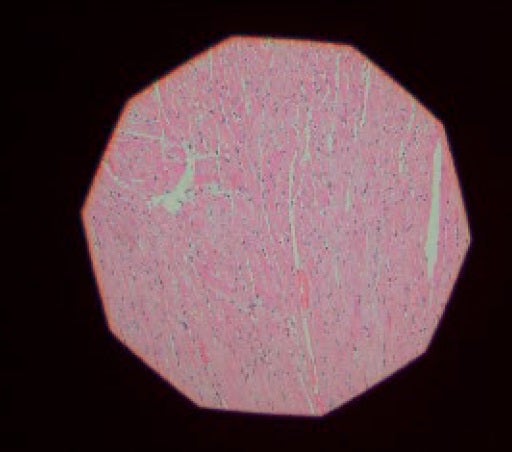

ICSI (Relief contrast)

ICSI (Reliefkontrast)

Das IX3-ICSI System wurde entwickelt, um die Anwendung der intrazytoplasmatischen Spermieninjektion (ICSI) als Teil des In-vitro-Fertilisationsverfahrens (IFV) zu erleichtern. Das Relief-Kontrastverfahren von Olympus ermöglicht die 3D-Oozytenbetrachtung in Kunststoffschalen zur Überprüfung des Zustands der Zona pellucida. Das teilmotorgesteuerte IX3-System verfügt über einen speziellen Handschalter für ICSI, mit dem die Betrachtungsmethode und die Vergrößerung auf Tastendruck geändert werden können. Die Polarisationsmethode dient der Betrachtung der meiotischen Spindel und ihrer Position, um so die Reife der Eizelle zu bestätigen und eine Beschädigung während der Injektion zu vermeiden, während die intrazytoplasmatische morphologisch selektierte Spermieninjektion mit der DIC-Methode (differenzieller Interferenzkontrast) durchgeführt wird.

• Optimiert für einen effektiveren Ablauf der ICSI

• Einfache Überprüfung des Zustands der Eizelle durch Spindelvisualisierung

• Optimierte ICSI-Schritte durch motorgesteuerte Bedienung